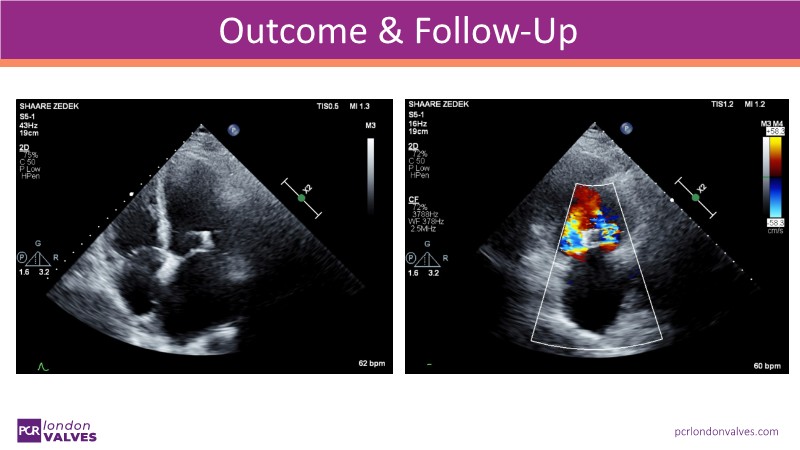

This LIVE case symposium brings mitral regurgitation guidelines into real clinical practice. Through step-by-step patient demonstrations and insightful discussion, the session explores how recommendations guide decision-making in ventricular and atrial secondary MR, how the heart team tailors therapy to individual anatomy and comorbidities, and how device iterations and procedural workflow can influence outcomes.

From medical optimisation to TEER selection and surgical considerations, the session highlights the reasoning behind each treatment choice. Watch now to find out more!